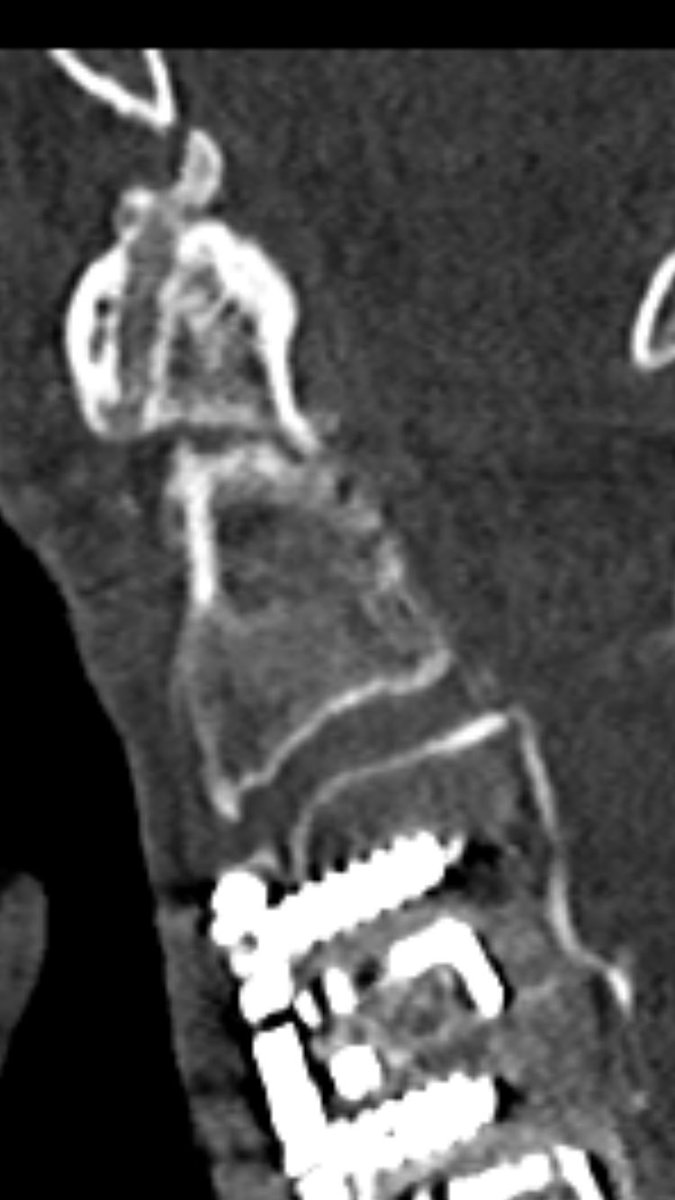

follow up after 8 weeks (l) and 6 month (r) show non-union, as expected. It’s a pseudarthosis.

but he was painfree right after 2 month.

You can nicely see signs of remodelling, but the fracture line still remains.

after 16 month, remodelling is still ongoing: surprisingly the atlantodental joint is now ankylosed and the fracture line is narrowed, but still not fused.

he had no pain, and a subjective sufficient function for daily activities. he was fine!

(CT was performed for other reason)